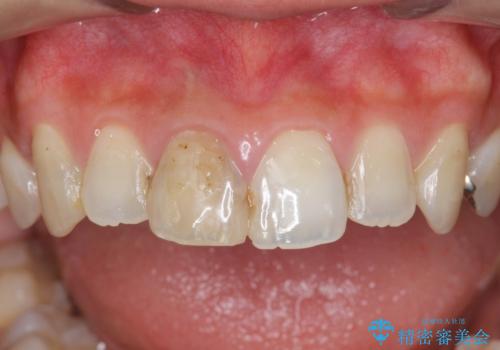

前歯をきれいにしたい

- 「 以前神経を取った歯の変色が気になる。前歯をきれいにして欲しい。」と治療を希望され来院されました。

目立つ上顎前歯に変色・大きな虫歯治療痕が見られ、審美障害を引き起こしています。